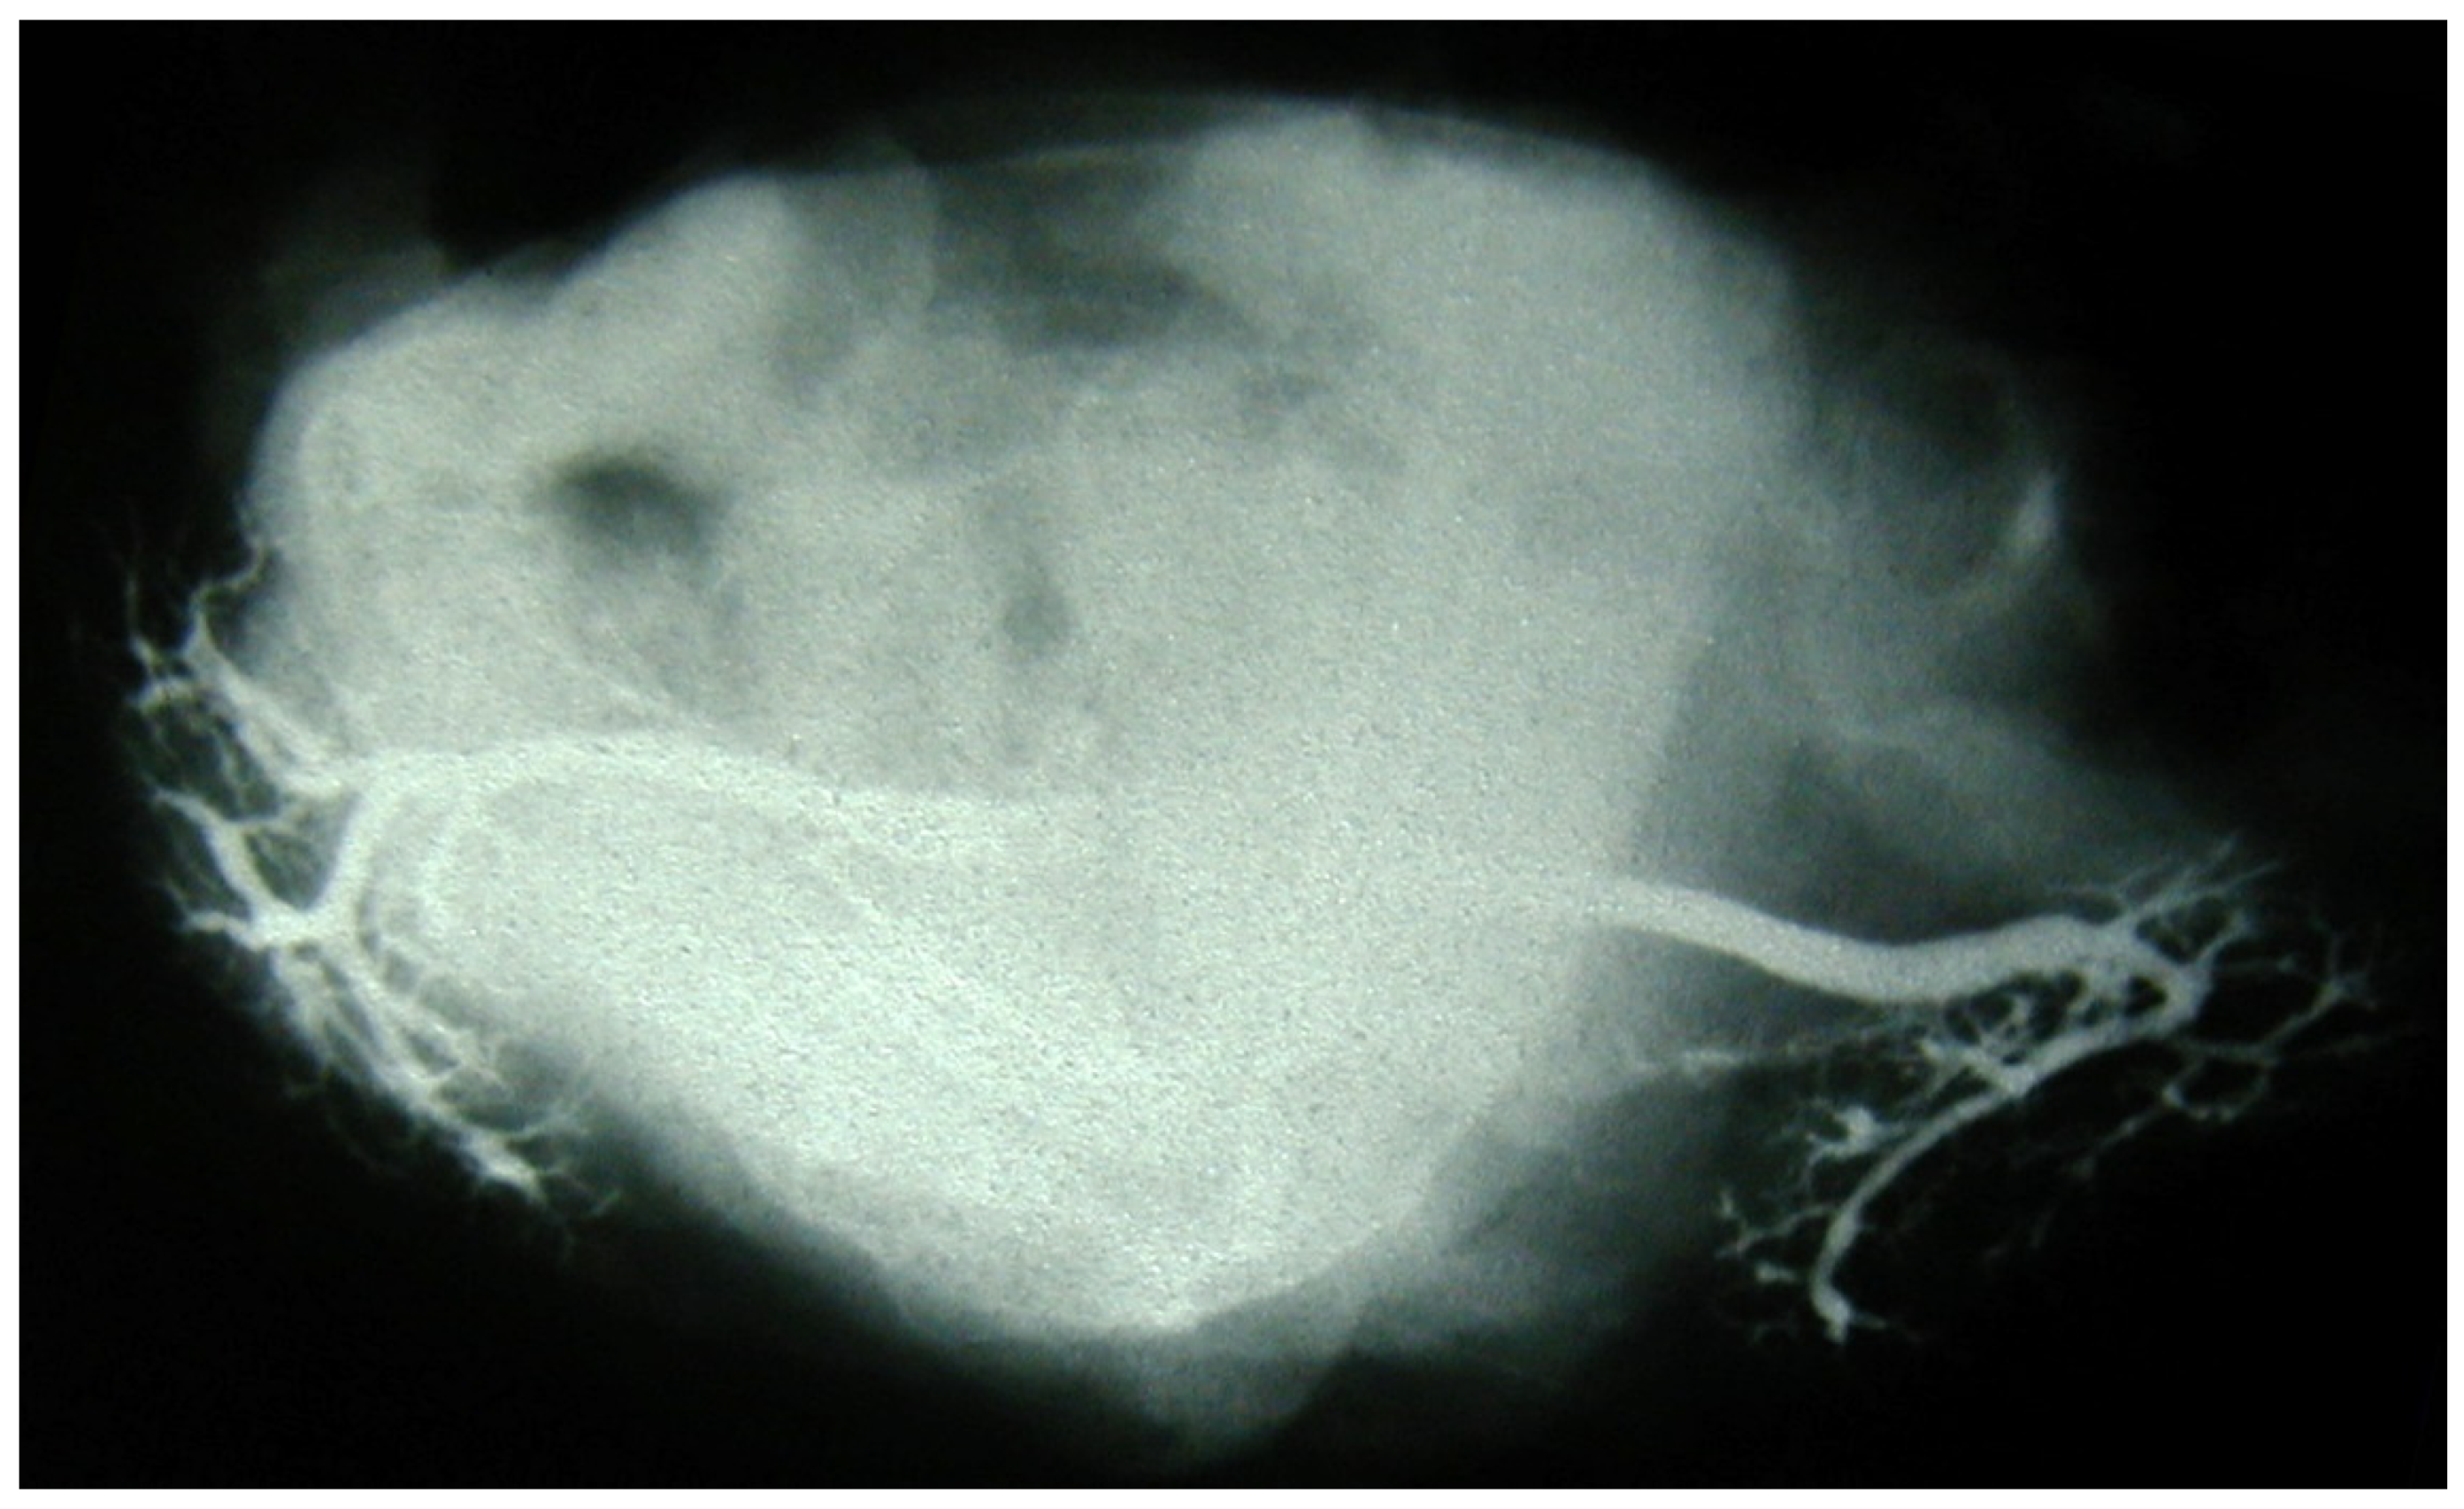

Immediately after injection, the specimens underwent image acquisition on standard radiographic equipment. Their positions in the frontal and the axial planes were controlled beforehand and verified via fluoroscopy (Figure 1 and Figure 2). A metal reference lamina of known width was placed in the vicinity of the specimen, for the purpose of the calibration of dimension, i.e., resolving the magnifying influence of distance between the X-ray tube and the specimen (film). Sialograms were taken under the following parameters: a generator of 42–50 kV and exposure of 3.2–5.0 mAs.

Figure 1. Postmortem sialography of submandibular glands, coronal plane. The ductal arborization is distinct. Hyoid bone is visible in the middle of the image.